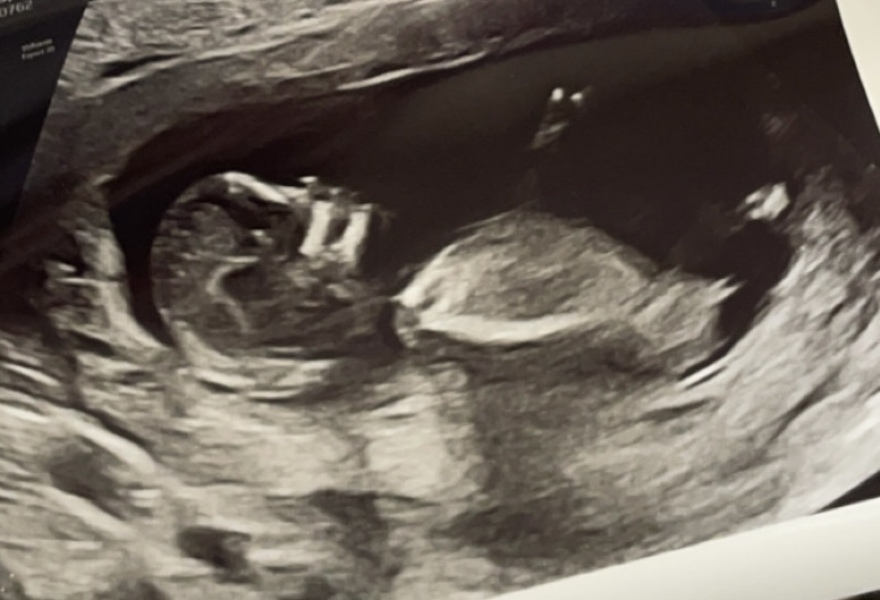

13 week scan, finding out in 4 weeks the gender but what’s everyone’s thoughts from scan photo. Boy or girl?